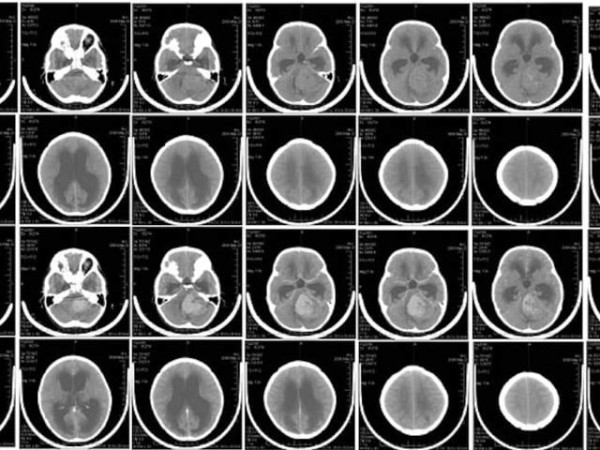

برازیلی ماہرین نے نہایت کم خرچ نظام بنایا ہے جو بچوں اور نوعمروں میں میڈیولوبلاسٹوما کی چار مختلف اقسام کی شناخت میں مدد دیتا ہے۔ اسی بنا پر ڈاکٹر طریقہ علاج اختیار کرتے ہیں۔ فوٹو: وکی میڈیا